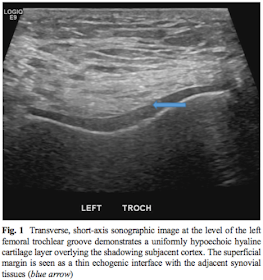

- ヒアリン軟骨は低エコーだが(figure1)、線維軟骨は高エコー(figure2)